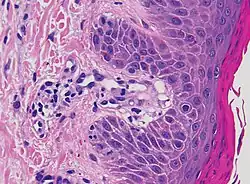

| Kaposi’s sarcoma in patch stage | The patch stage typically shows irregular proliferation of jagged vascular channels in the dermis below an integral epidermis. The so-called promontory sign is sometimes found in patch stage lesions and denotes vascular spaces surrounding pre-existing blood (see image).[23]

vessels |

|